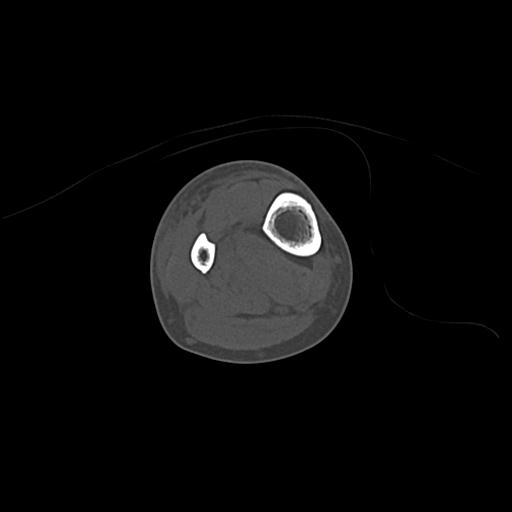

82084 1/14 1/20 股関節 2R 78歳男性 右人工骨頭